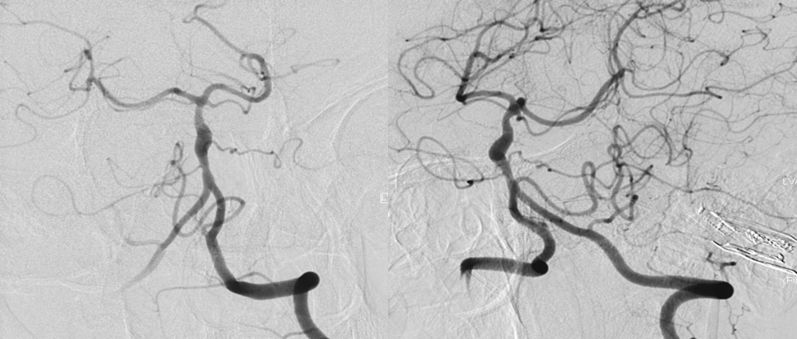

本院DSA:基底动脉巨大夹层动脉瘤,双侧后交通动脉未见明显开放(图6)。

图6

2、头部核磁共振显示:脑干占位性病变,边界较清晰,较大层面大小约35 mmx25 mm。MRA显示:基底动脉夹层动脉瘤。DSA显示,基底动脉巨大夹层动脉瘤,最大长径为:10.8 mm,最大短径为3.2 mm。根据患者症状及影像学诊断,基底动脉巨大夹层动脉瘤进行性增大压迫脑干,不排除脑干水肿可能,亟待手术治疗。

3、由于双侧后交通动脉未见明显开放,为保证脑干血供,手术必须确保载瘤动脉通。动脉瘤累及左侧AICA,基底动脉穿支丰富,位置深在,而且动脉瘤为夹层动脉瘤开颅手术治疗困难,且风险极高。回顾文献及本中心治疗经验,此类动脉瘤血流导向装置疗效较好,经科内讨论后决定运用Tubridge血流导向装置治疗。